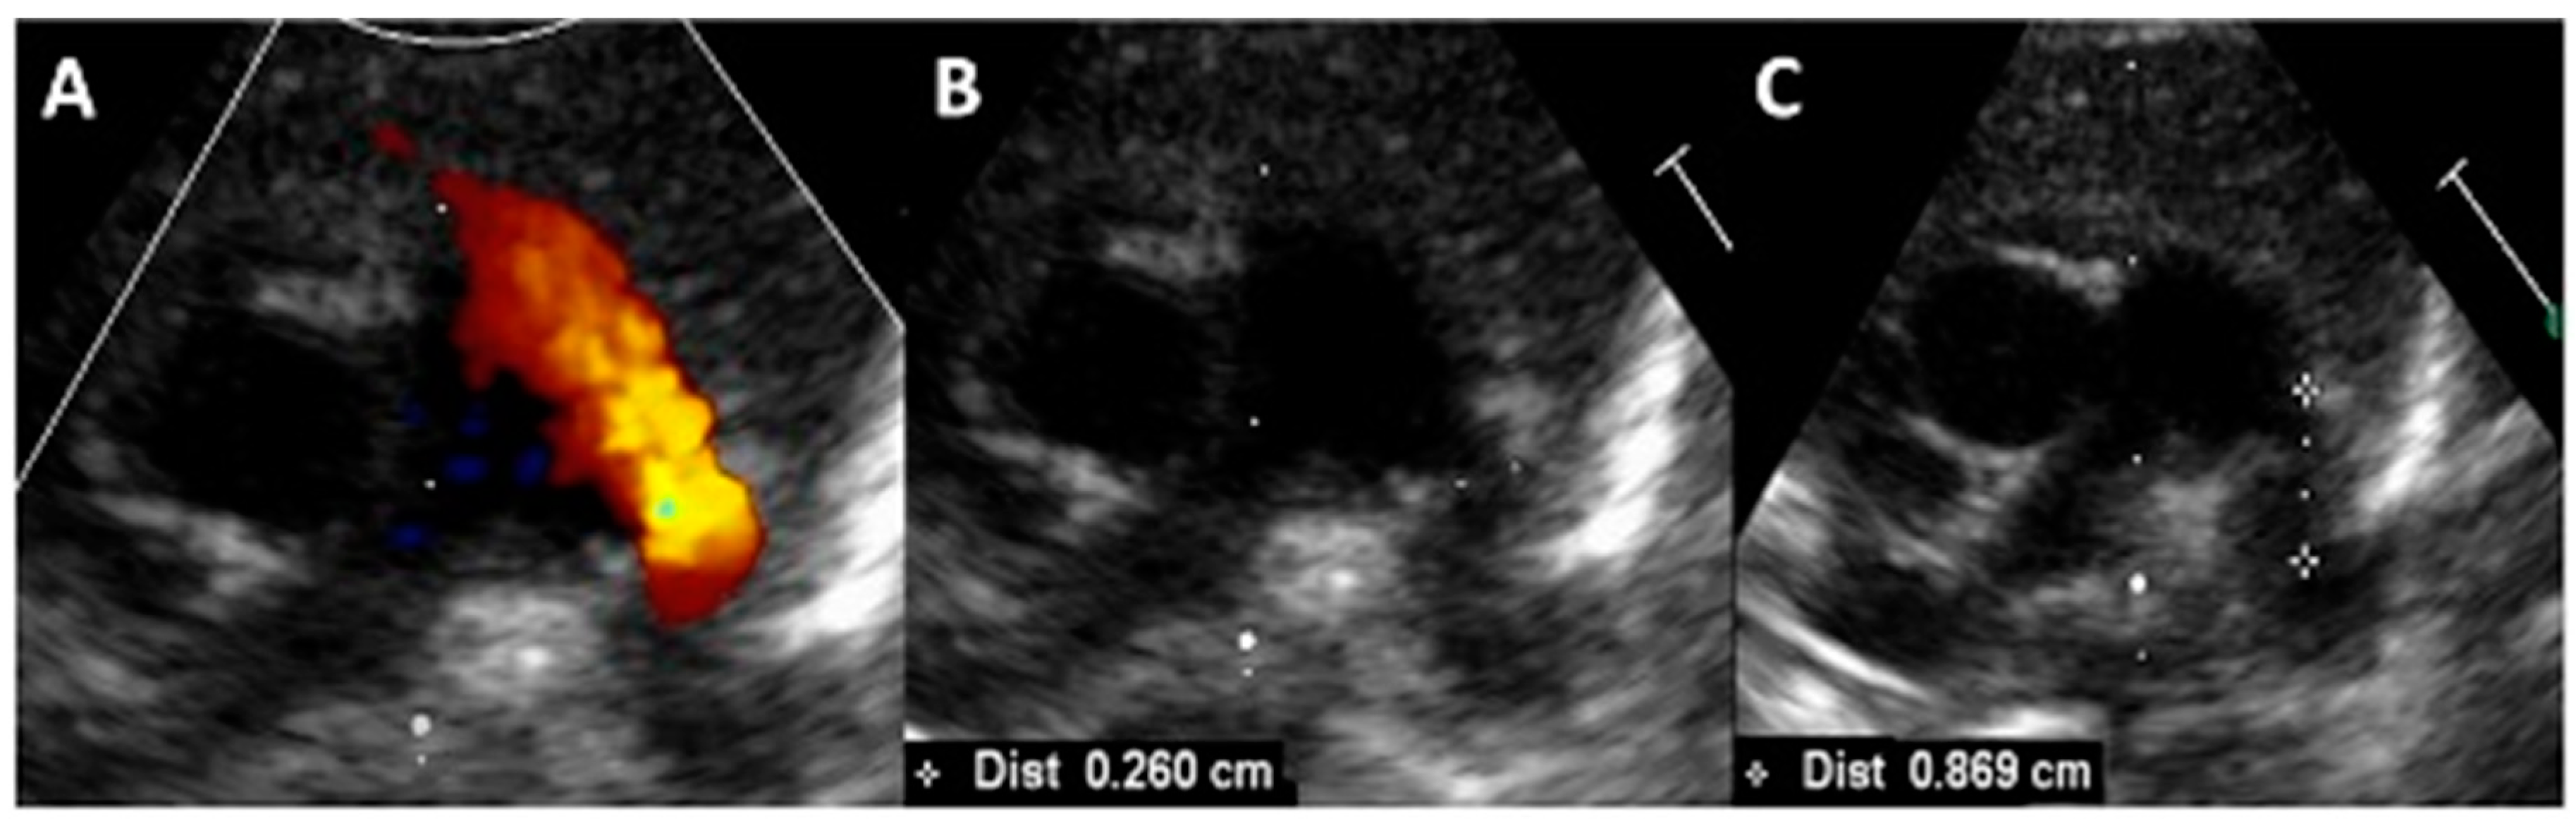

- Padovani, P.; Benbrik, N.; Baruteau, A.-E. Late aortic obstruction due to ductal vasoconstriction on pulmonic end after transcatheter patent ductus arteriosus closure in an extremely low-birth-weight infant. Cardiol. Young 2023, 33, 2113–2115. [Google Scholar] [CrossRef]